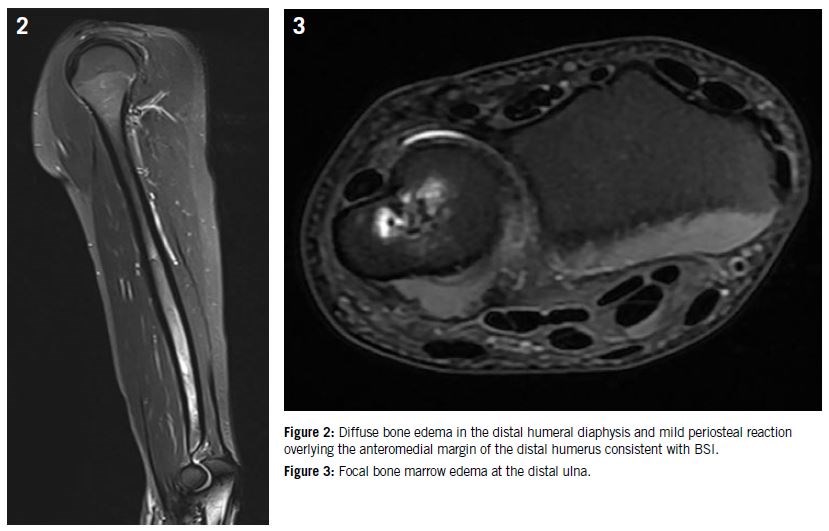

Stress injuries of the humerus often involve the proximal, middle, and distal thirds of the bone, depending on the repetitive mechanical forces applied16,28. A notable injury, known as “Thrower’s fracture”, is a spiral stress fracture commonly seen in baseball pitchers due to repetitive torsional stress29. Ulnar neuropathy can sometimes masquerade as a humeral stress fracture, complicating clinical diagnosis15. Symptoms typically include mid-arm pain aggravated by throwing activities, often accompanied by neural symptoms such as tingling or numbness. MRI remains the diagnostic modality of choice39 (Figure 2). Conservative management with rest followed by structured rehabilitation and gradual return to throwing programs is the standard treatment protocol3,40.

Figure 2: diffuse bone edema in the distal humeral diaphysis and mild periosteal reaction overlying the anteromedial margin of the distal humerus consistent with BSI

Ulna stress fractures are prevalent among gymnasts and weightlifters, frequently involving the shaft due to repetitive axial loading combined with hyperextension30–32. Clinical presentation includes dorsal forearm pain exacerbated by activity, specifically resisted wrist extension or forearm rotation. MRI and bone scintigraphy are critical in diagnosing these subtle fractures early46 (Figure 3). Conservative management, including immobilization and activity modification, typically leads to successful healing3.